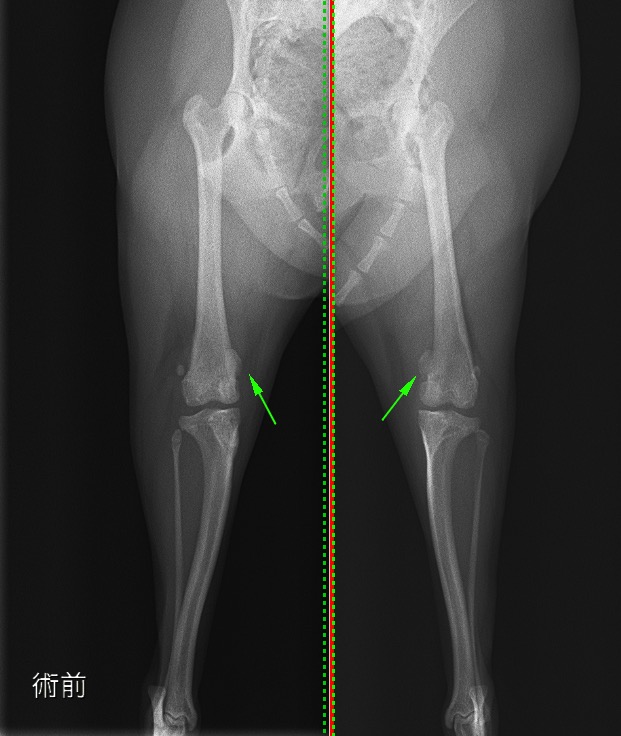

術前のX線検査では左右共に膝蓋骨内方脱臼が認められました。(緑矢印)

術前のX線 左右共に膝蓋骨が内方脱臼している(緑矢印)